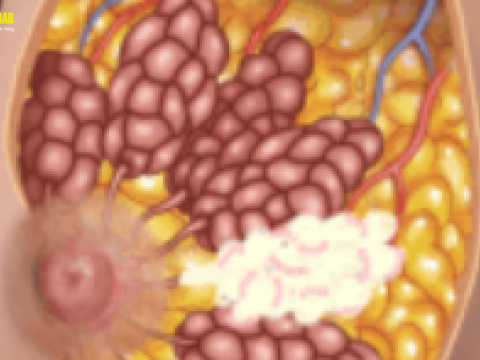

Điều trị viêm tắc tia sữa